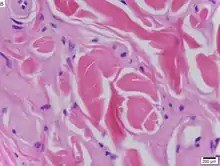

| Urbach–Wiethe disease in skin biopsy with H&E stain. | |

The dermatological symptoms are caused by a buildup of a hyaline material in the dermis and the thickening of the basement membranes in the skin.[9] The nature of this material is unknown, but researchers have suggested that it may be a glycoprotein, a glycolipid, an acid mucopolysaccharide, altered collagen or elastic tissue.[6]